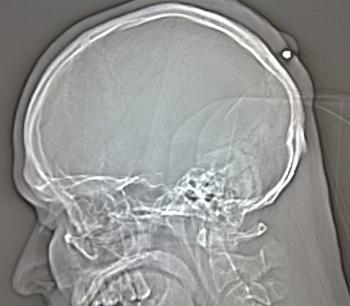

Herne/Bochum 24. augusta (TASR) - Istý 35-ročný Nemec žil niekoľko rokov bez akýchkoľvek problémov s projektilom o veľkosti necelých päť milimetrov v hlave. Náboj pochádza pravdepodobne z pištole neznámeho strelca, ktorý v uliciach mesta Herne v Severnom Porýní-Vestfálsku oslavoval príchod nového roku.

Keď mu lekár objavil v priebehu tohtoročného leta opuch na zátylku, poslal ho na röntgenové vyšetrenie, ktoré odhalilo prítomnosť cudzieho predmetu pod pokožkou hlavy, nie však v lebečnej kosti. Stačil tak malý zákrok a projektil bol vonku, informovala dnes agentúra DPA s odvolaním sa na políciu z mesta Bochum.